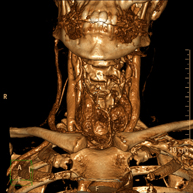

- Neck CT

Radiological test that provides high definition anatomical images of the neck using CT (Computed Tomography) equipment. Indicated for: thyroid study, control of treated tumours, study of lymph nodes, infections and abscesses.

- Angio – Supra-Aortic Trunk CT

Radiological test that provides high definition anatomical images of the carotid arteries of the neck using CT (Computed Tomography) equipment and the injection of an intravenous contrast agent. The images are then reconstructed in three dimensions (3D). Indicated for: acute cerebral vascular accident, transient vascular accident, carotid bruit.